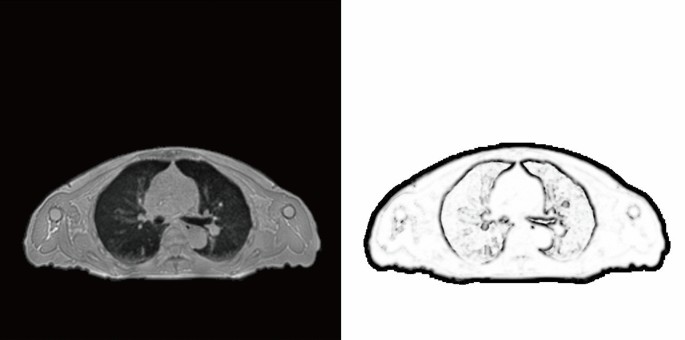

where N denotes the 3-neighbourhood of voxel x. The left image in Fig. 2 presents the original ZTE MRI while the corresponding right image presents MIND. The outlines of the body surface, lungs, bones, and blood vessels in the lungs were extracted.